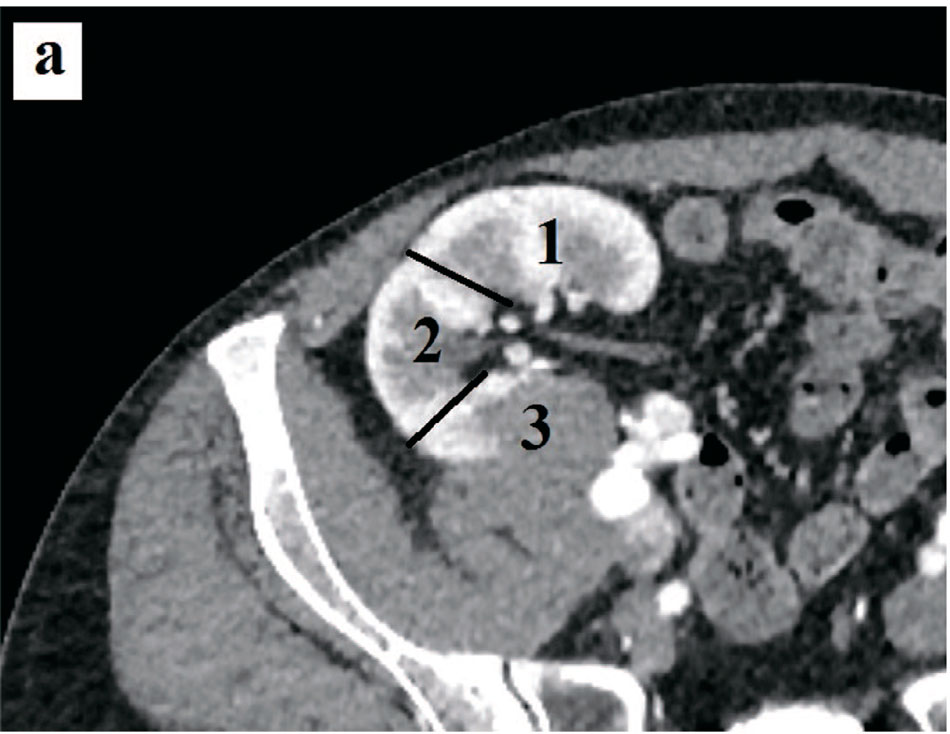

В данном случае критерий A в модифицированной шкале имеет 3 балла, так как опухоль расположена по задней поверхности, в зоне трудно доступной для резекции, тогда как в шкале R.E.N.A.L. для нативной почки у критерия А балл не определяется, а обозначается постфиксом (а, р, х или h) (рис. 5.).

Рис. 5. Пациент А. Компьютерные томограммы пациента с образованием трансплантированной почки (критерий A и L): а – аксиальная проекция, б – коронарная проекция. Разделение на поверхности: 1 – передняя, 2 – ребро почки, 3 – задняя. Разделение на сегменты: а – верхний, б – средний, в – нижний.

Fig. 5. Patient A. Computer tomograms of a patient with the formation of a transplanted kidney (criterion A and L): a – axial projection, b – coronal projection. Division into surfaces: 1 – anterior, 2 – kidney rib, 3 – posterior. Division into segments: a – upper, b – middle, c – lower

Последний критерий L также будет иметь максимальный балл 3, так как опухоль расположена в нижнем сегменте, представляющим значительную трудность для резекции в силу сложности при мобилизации из-за топографии и рубцового процесса (рис. 5). Тогда как в случае соответствующего расположения опухоли в нативной почке по шкале R.E.N.A.L. опухоль будет иметь наименьший балл 1, так как расположена ниже полюсных линий.